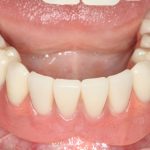

Рекомендации по установке имплантов. Для всех. Часть III